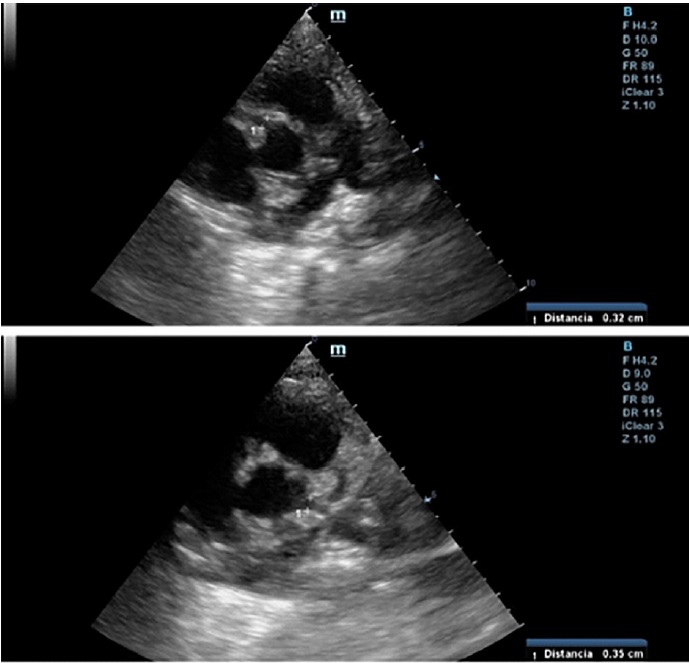

A las 24 horas del alta presenta registro febril, regular estado general, acompañado de lengua aframbuesada, edema bipalpebral y conjuntivitis. Se interna. Por laboratorio se constatan parámetros de inflamación, IgG para SARS-CoV 2 positivo y al repetir ecocardiograma Doppler (Figura 1) presenta dilatación aneurismática de ambas coronarias con función ventricular conservada (Tabla 1, se detallan los valores de las coronarias con sus respectivos Z score, en los sucesivos controles ecocardiográficos). Se reasume el cuadro como SIM-C. Recibe tratamiento inmunomediado y antiagregante plaquetario con gammaglobulina (2 gr/kg/dosis), metilprednisolona (10 mg/kg/dosis, 3 pulsos), AAS 5 mg/kg/día. Presenta leve mejoría clínica y analítica. El control cardiológico a los 5 días revela similares características. Se lo clasifica como resistente al tratamiento y se indica Infliximab (5 mg/kg). Evoluciona favorablemente, con marcada mejoría clínica y cardiovascular; se otorga el alta luego de 16 días. Se programa control cardiológico y reumatológico más tratamiento antiagregante y antiinflamatorio.

Fig. 1 Ecocardiograma Doppler 2D (eje corto de los vasos): se observa coronaria derecha en la parte superior, y coronaria izquierda en la inferior.